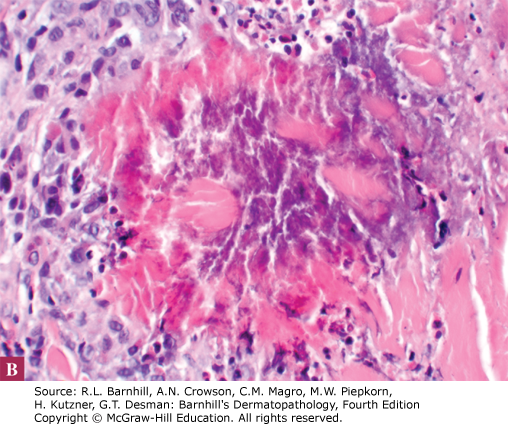

Rationale: Recognizing the type of infiltrate in dermatopathology slides can help categorize rashes and narrow the differential diagnoses. All the answer choices have very different patterns (vascular growth in pyogenic granuloma) and different types of inflammatory infiltrate (neutrophilic, eosinophilic, granulomatous, or lymphocytic). Identifying eosinophils and flame figures in the photographs above is critical to the identification of the correct diagnosis.

The photographs above demonstrate perivascular mixed infiltrate with multiple flame figures. Flame figures represent degranulated eosinophils. Wells syndrome presents clinically as erythematous papules and plaques that can appear similar to cellulitis and are typically pruritic. Flame figures are not pathognomonic for Wells syndrome and can be seen in other eosinophilic processes such as arthropod reaction, allergic contact dermatitis, and bullous pemphigoid. Patients diagnosed with Wells syndrome should be evaluated for underlying malignancy, medication reaction, or parasitic infections.